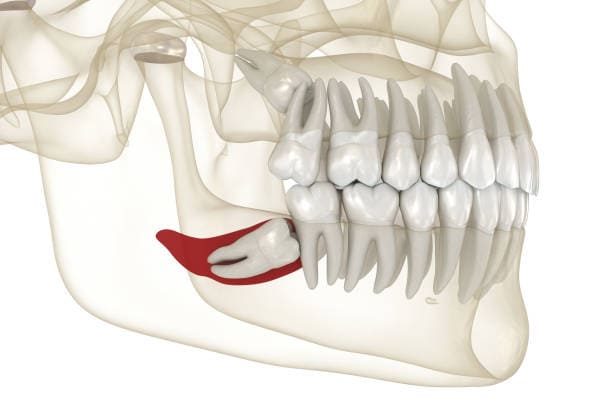

Why Are Wisdom Teeth Removed?

- Pain and Discomfort : Impacted wisdom teeth can cause severe pain and swelling

- Crowding and Misalignment :Wisdom teeth can push other teeth out of alignment.

- Cyst Formation :In some cases, impacted teeth may develop cysts, damaging surrounding bone and teeth.

- Wisdom teeth, also known as third molars, are the last set of molars to emerge, typically in the late teens or early twenties. While these teeth can sometimes align properly, they often cause issues such as pain, crowding, or infection, necessitating removal.